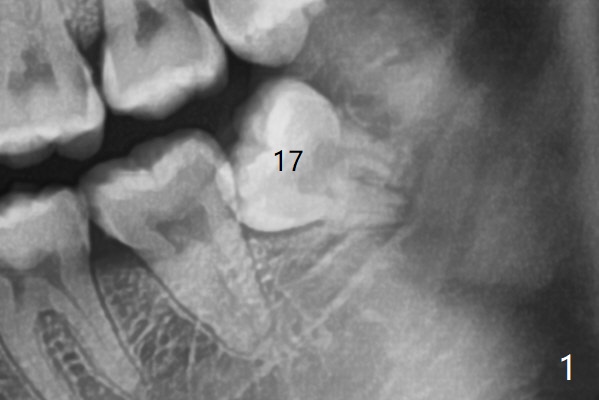

A 24-year-old woman with poor oral hygiene presents to clinic requesting extraction of the tooth #17 (Fig.1). The tooth is removed after multiple sectioning. One half of collagen plug is placed in the bottom of the socket (Fig.2 C, while 1 cc of Bond Apatite in the coronal portion of the socket (A). The other half of the collagen plug is placed on the top of the cement before suturing with 4/0 PGA. The patient feels pain when the tooth is wiggled heavily. But the Inferior Alveolar Canal is not exposed when the tooth is out.